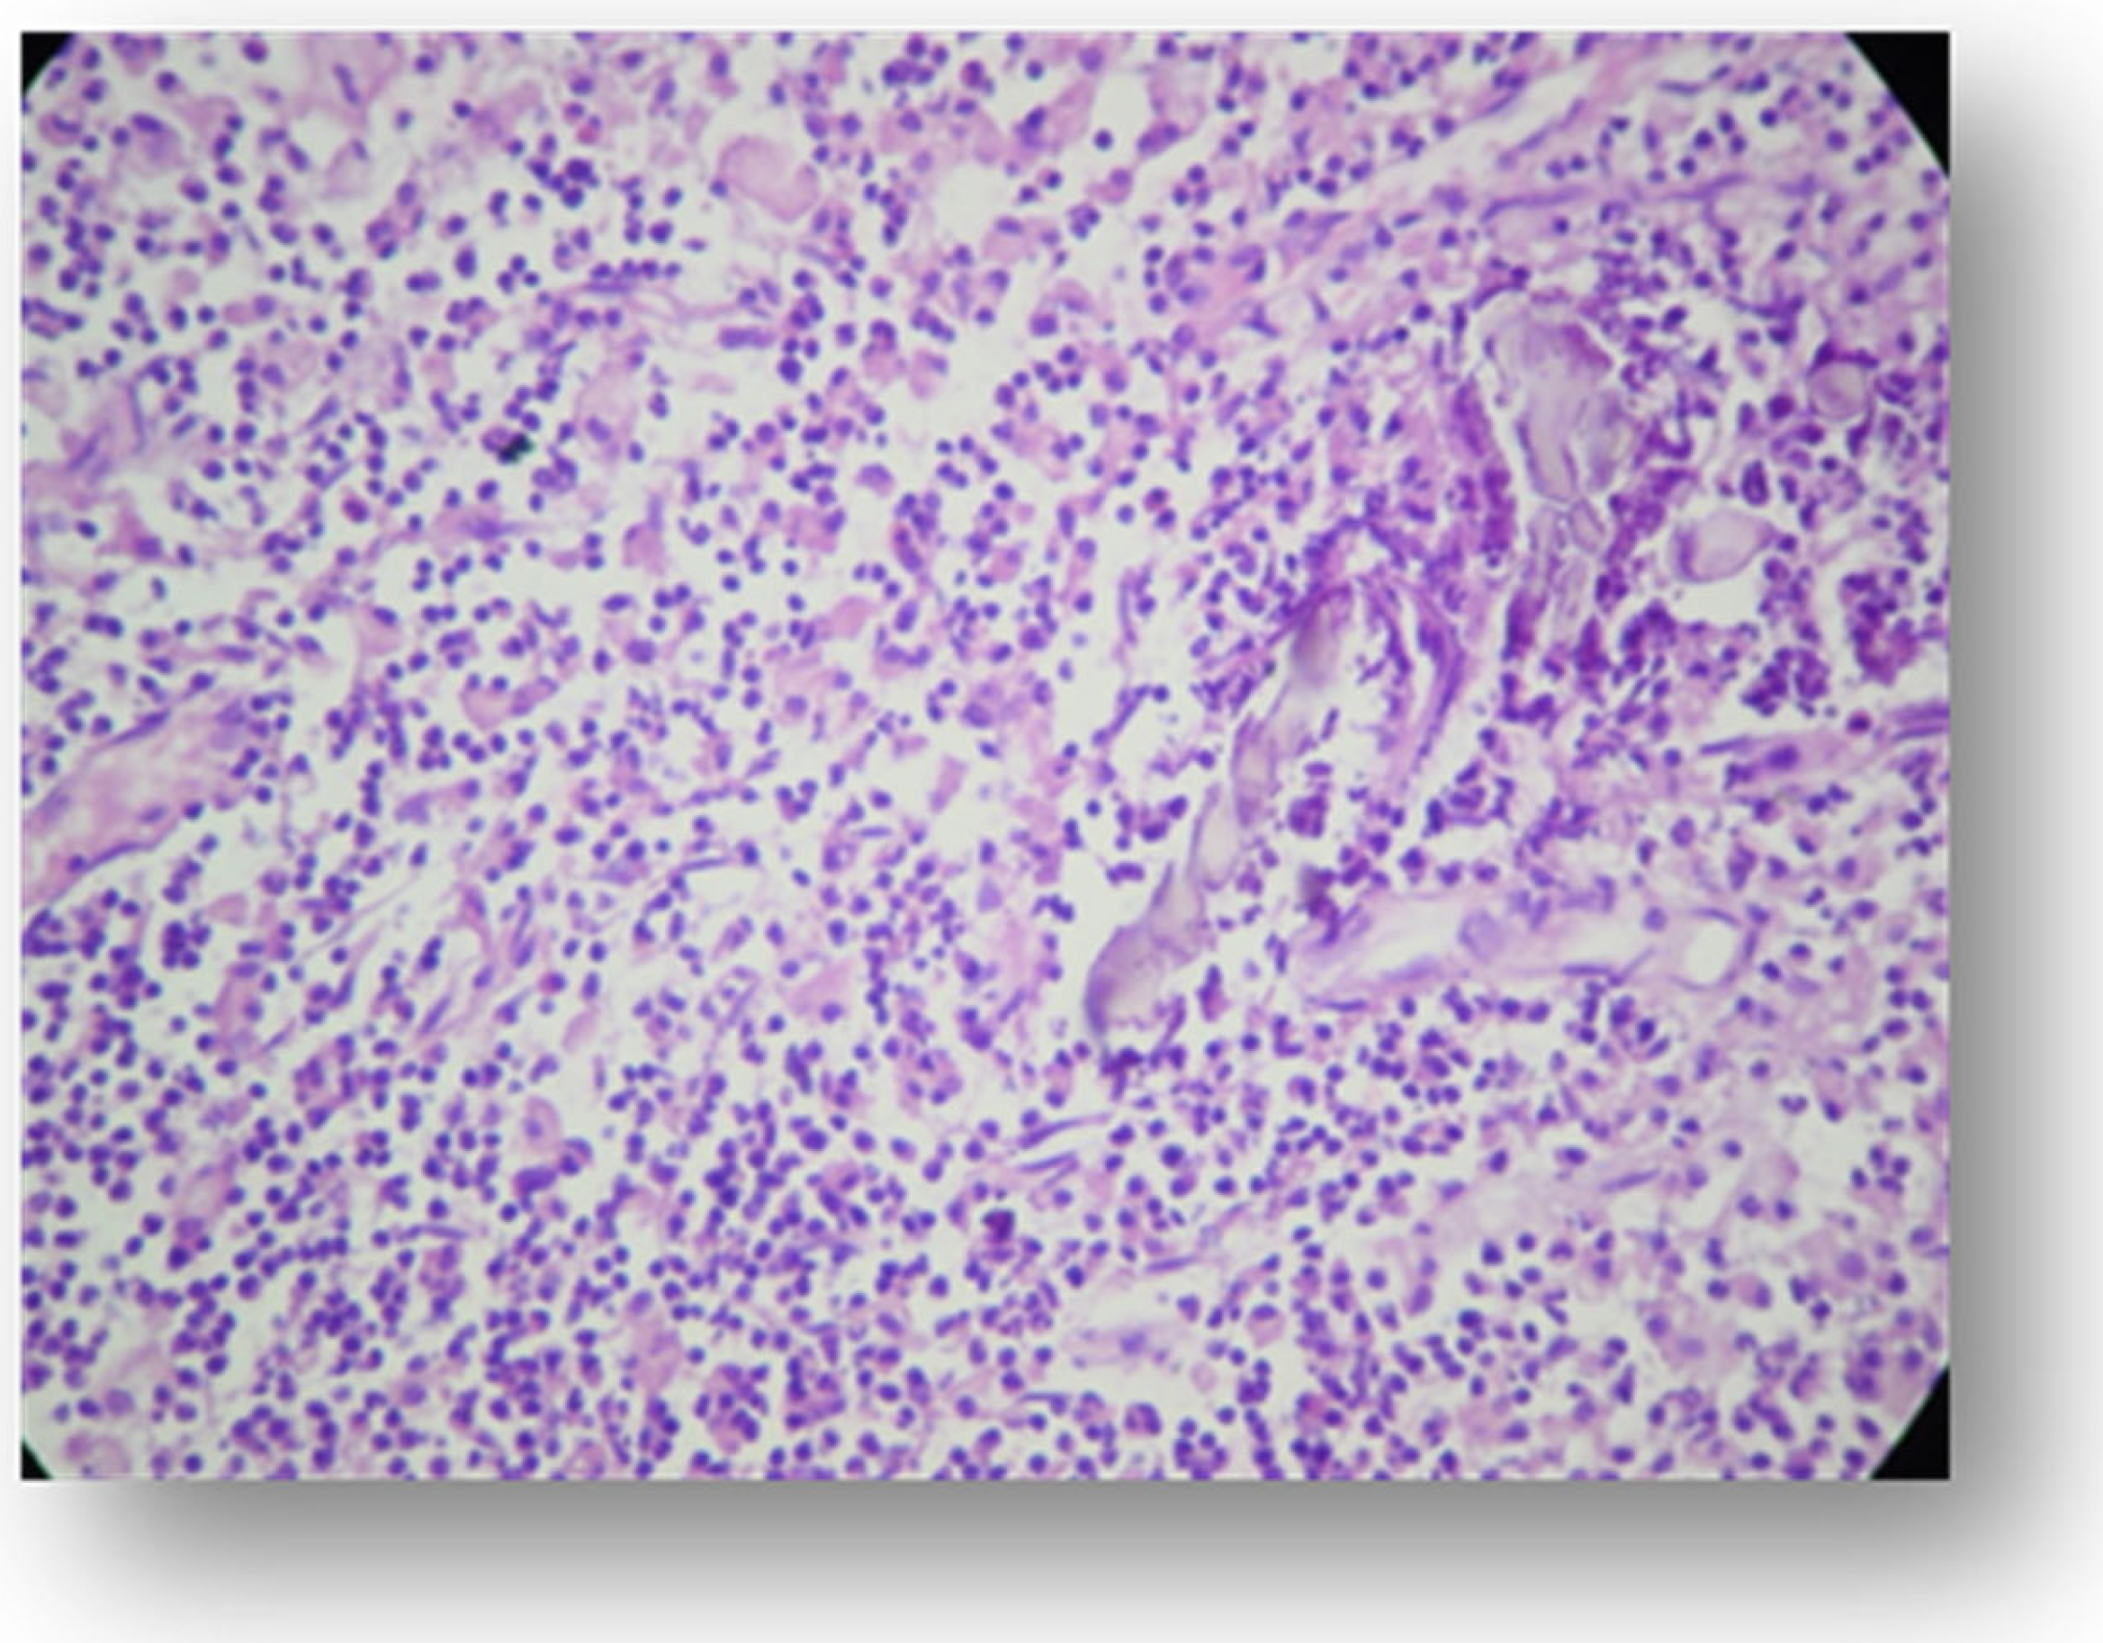

- Moraru, A.I.; Gheorghiţă, L.M.; Dascălu, I.T.; Bătăiosu, M.; Manolea, H.O.; Forna, D.A.; Râcă, A.M.; Raţiu, C.A.; Diaconu, O.A. Histological and immunohistochemical study on the dental pulp of patients with diabetes mellitus. Rom. J. Morphol. Embryol. = Rev. Roum. Morphol. Embryol. 2017, 58, 493–499. [Google Scholar]

- Shetty, P.; Mulay, S.; Singh, M.; Singh, M.; Reddy, M.; Chawla, M.; Shaikh, M. Histological changes in dental pulp of diabetes mellitus (type II). Int. J. Curr. Res. 2017, 9, 57815–57818. [Google Scholar]